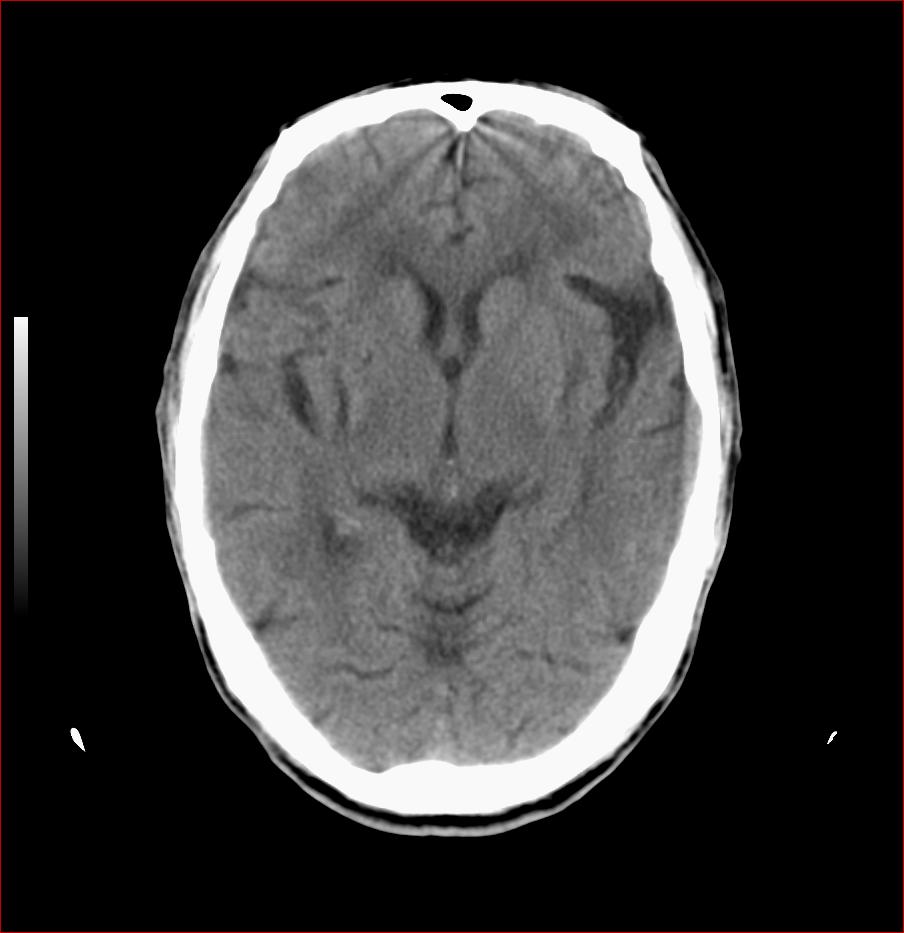

男,84岁,左下肢无力伴口角歪斜1天,血压160/80。请问一下双侧基底节区是脑梗塞吗?

多发脑梗塞,白质疏松,脑萎缩

双侧基底节多发腔梗,皮层下动脉硬化性脑病

老年性三联症_多发腔隙性梗死 脑萎缩 脱髓鞘变性.

双侧基底节多发腔隙性脑梗塞;脑白质蔬松;脑萎缩。

1.两侧基底节区及右顶深部脑梗塞。2.右侧外囊区脑软化灶。3.脑萎缩。4.脑白质脱髓鞘改变。

1.双基底节区及双顶深部脑梗塞;2.右外囊区软化灶;3.皮层下动脉硬化性脑病.

1 两侧基底节区脑梗塞;

2 右侧壳核区脑软化灶;

3 脑白质脱髓鞘;

4 脑萎缩。